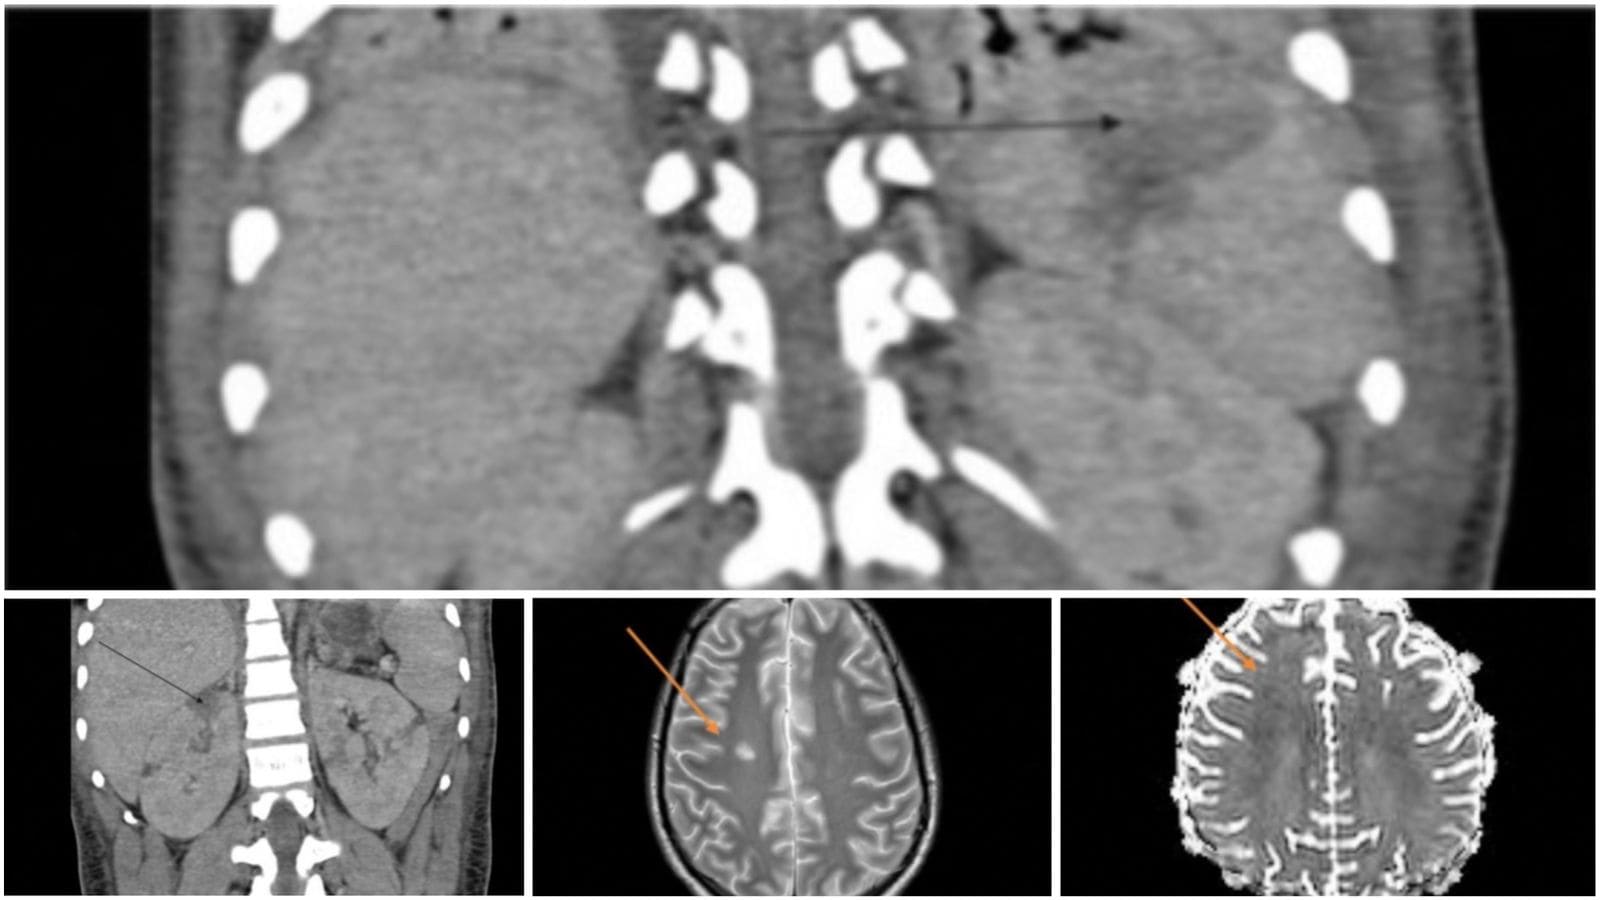

El paciente completó un ciclo de antibióticos y continuó con una pauta descendente de corticoides. Fue dado de alta del hospital con una notable recuperación global, aunque persistió una leve debilidad en la extremidad inferior izquierda como secuela neurológica. Una resonancia magnética cerebral realizada de control reveló la presencia de pequeños infartos lacunares, explicando el déficit residual.

La afectación cardíaca con miocarditis grave y la encefalopatía con infartos lacunares completan el espectro de una enfermedad sistémica severa.